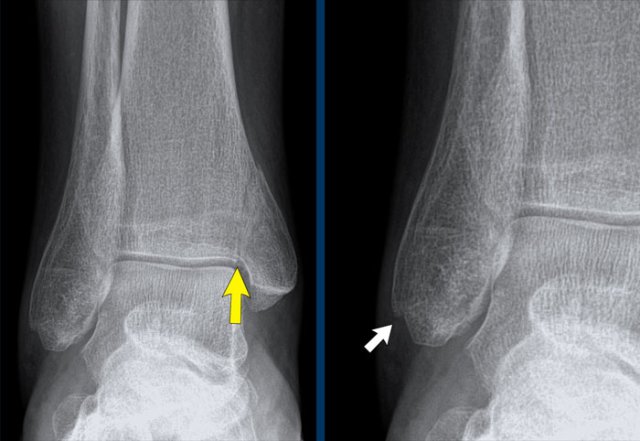

case 3 - distortion

This is another case of a fracture of the posterior malleolus.

Again we have to look at the algoritm for ankle fractures...

A fracture of the posterior malleolus is seen in a Weber B or a Weber C fracture.

In this case we have already seen an oblique fracture of the lateral malleolus, which means that we are dealing with a Weber b fracture.

Now we only need to determine which stage it is.

The most common stage 2 is stable, but stage 3 and 4 are unstable.

In this case we already in stage 3 and we wanna look for signs of stage 4.

A painful soft tissue swelling at examination would already indicate stage 4, but in this case there is more.

Maybe you want to go back to the radiograph before you continue reading...

In this case we are looking for a stage 4.

Now you notice the soft tissue swelling on the medial side (arrow).

The most important finding however is the irregularity and radiolucency of the upper part of the medial malleolus.

If you use your imagination, you can identify a fracure line here, which you would not have seen if you did not use the algoritm.